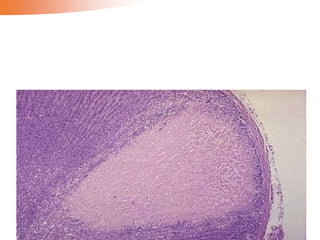

Fibrin thrombi

are visible

within

capillaries

 Fibrin thrombi in a glomerulus